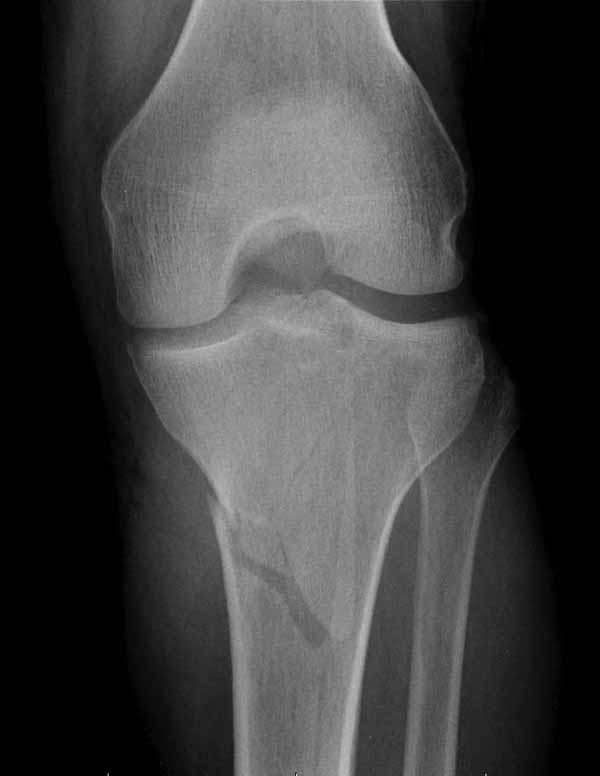

Двухколоннный перелом тибиал плато с вовлечением проксимального диафиза. Внутрисуставной компонент без смещения, и такой перелом можно лечить любым из описанных методов, о которых говорят наши коллеги.

Как понял, аппарат Илизарова не рассматривается предпочтительным для фиксации методом, хотя на фоне отека было бы идеальным для данного перелома. Для пластины требуется идеальная кожа, иначе наличие “суперсовременных имплантов” не поможет, и могут развиться серьезные осложнения.

Если у вас, кроме пластины, нет другого альтернативного варианта, тогда, учитывая мягкотканые проблемы с наружной стороны, я бы рекомендовал операцию делать в два этапа. Преимущества, сперва репозиция и фиксация перелома с медиальной стороны, а затем, после улучшения состояния мягких тканей, зафиксировать с латеральной стороны. Современные пластины имеют латеральный Jig для перкутанных мини доступов.

В приложении этапы фиксации Both Column Fx и пластиной Synthes для плеча при переломе медиального мыщелка.